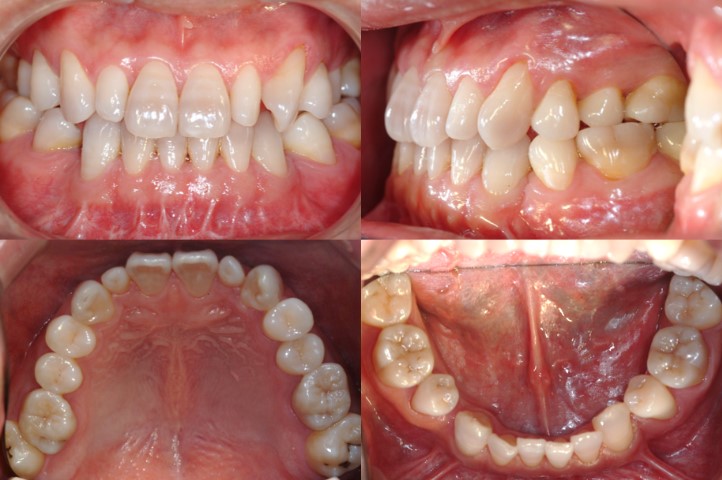

하악 편악발치를 하였으나, 어금니 반대교합 등 다양한 문제가 보이는 상황